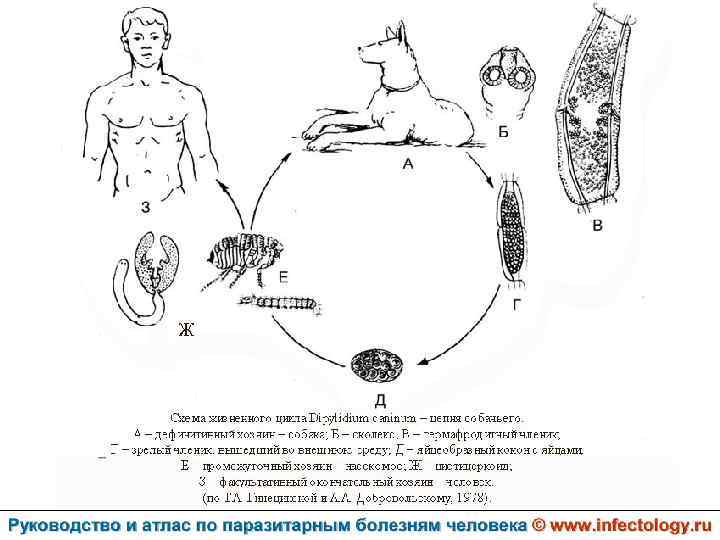

Дипилидиоз (шифр по МКБ 10 – B 71. 1) зоонозный биогельминтоз, характеризующийся аллергизацией организма и нарушением функций пищеварительного тракта.